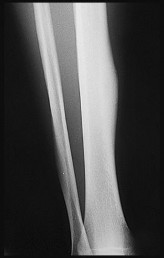

Question 17

A 32-year-old male sustains a closed tibia fracture and develops intense leg pain out of proportion to the injury. You suspect acute compartment syndrome.

Which of the following pressure parameters is considered the most reliable threshold indication for performing a four-compartment fasciotomy?